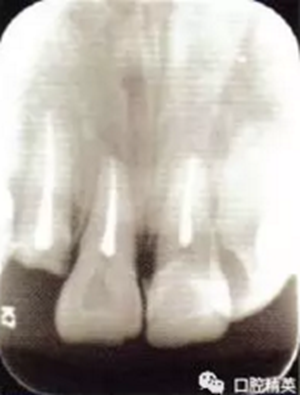

2冠根折,唇側(cè)斷端至齦下2mm,露髓,叩痛(+),不松,齦緣滲血;1冠折,未露髓,部分脫出,叩痛(+),松Ⅲ度,近中齦乳頭撕裂,長約1.5 cm;1挫入,切斷折斷,位于拉冠中部,叩診高調(diào)金屬音,不松,近中齦乳頭撕裂,長約1.5 cm;2見釉質(zhì)裂紋,叩痛(+),不松,齦緣滲血(圖1);以上牙齒X線均未見明顯根折線(圖2)。

圖2外傷牙鋼絲+釉質(zhì)粘接劑固定術(shù)后根尖片